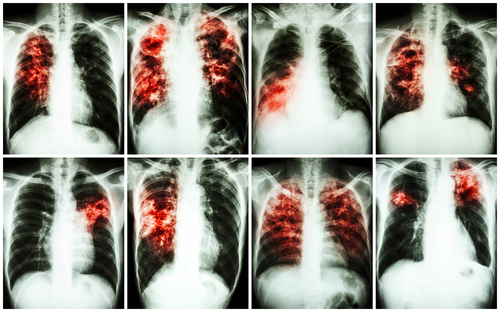

TBC je infekčné ochorenie, ktoré sa prenáša patogénom mycobacterium tuberculosis. Normálne napadá patogén pľúca, ale môže tiež prísť k infekcii ďalších orgánov. Choroba sa šíri vzduchom, keď chorí vypudzujú baktérie napr. pri kašli.